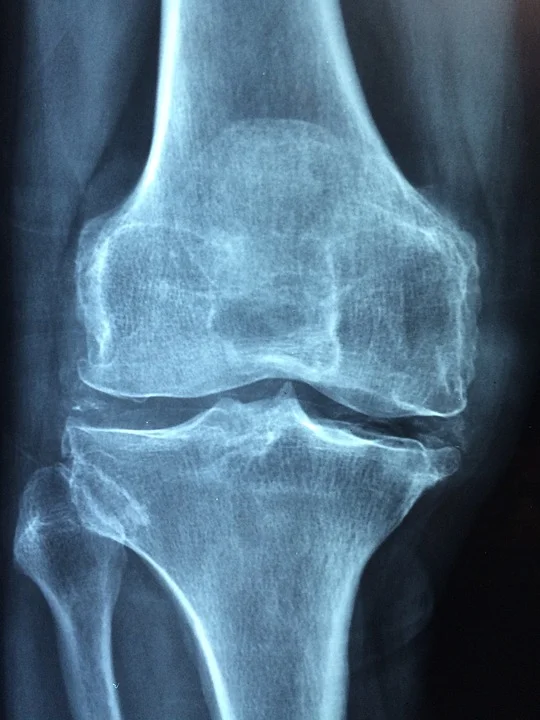

10. Promotes a Healthy Skeletal System

The endocannabinoid system has been implicated in the regulation of bone metabolism. R

Cannabinoid ligands regulate bone mass. R

CB1 and CB2 receptors have a protective effect against age-dependent bone loss in mice. R

Administration of CBD led to improvement in fracture healing. R

In humans, polymorphisms in CNR2, the gene encoding CB2, are strongly associated with postmenopausal osteoporosis. RR

Therefore CB2 agonists (like CBD) enhances endocortical osteoblast number helping osteoperosis. R

- CB1 receptor deficiency in aged mice results in accelerated age-dependent osteoporosis due to marked increase in bone resorption and significant reduction in bone formation coupled to enhanced adipocyte accumulation in the bone marrow compartment. R R

- Bone loss was also reported in CB2 deficient mice. R

- CBD stimulated mRNA expression of Plod1 in primary osteoblast cultures, encoding an enzyme that catalyzes lysine hydroxylation, which is in turn involved in collagen crosslinking and stabilization. R

- Co-expression of TRPV1, CB1/CB2, NAPE-PLD and FAAH was found in both human osteoclast cultures and in native osteoclasts from human bone biopsies. R

- Activation of CB1 in sympathetic nerve terminals in bone inhibits norepinephrine release, thus balancing the tonic sympathetic restrain of bone formation. R

- A CB2-specific agonist that does not have any psychotropic effects enhances endocortical osteoblast number and activity and restrains trabecular osteoclastogenesis, apparently by inhibiting proliferation of osteoclast precursors and receptor activator of NF-kappaB ligand expression in bone marrow-derived osteoblasts/stromal cells. R